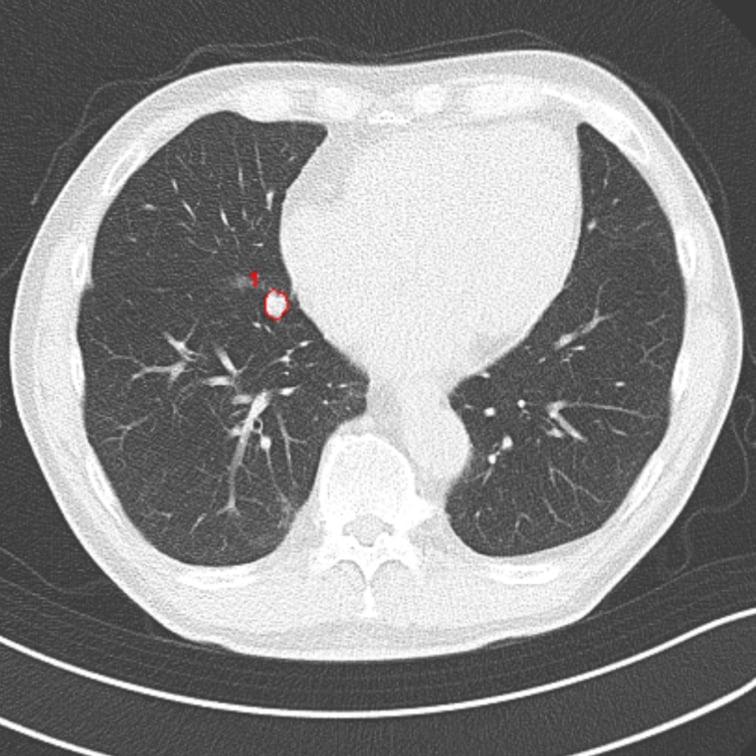

以下の肺結節候補領域を検出して表示します- 充実型:3mm以上30mm以下

- 部分充実型:5mm以上30mm以下

- すりガラス型:5mm以上30mm以下

- 自動計測

- 検出した候補領域の大きさ:体積 [mm³] およびAxial断面最大径 [mm] を出力

- CT値:最大・最小・平均値・標準偏差を出力

解析事例

低線量CT

* 低線量CTについて

通常のCTに比べ、被検査者に与える被ばく量を軽減することが可能です。一方、撮影される画像は、通常のCTに比べて質が低下する傾向にあり、読影診断の難易度が高まると言われています。